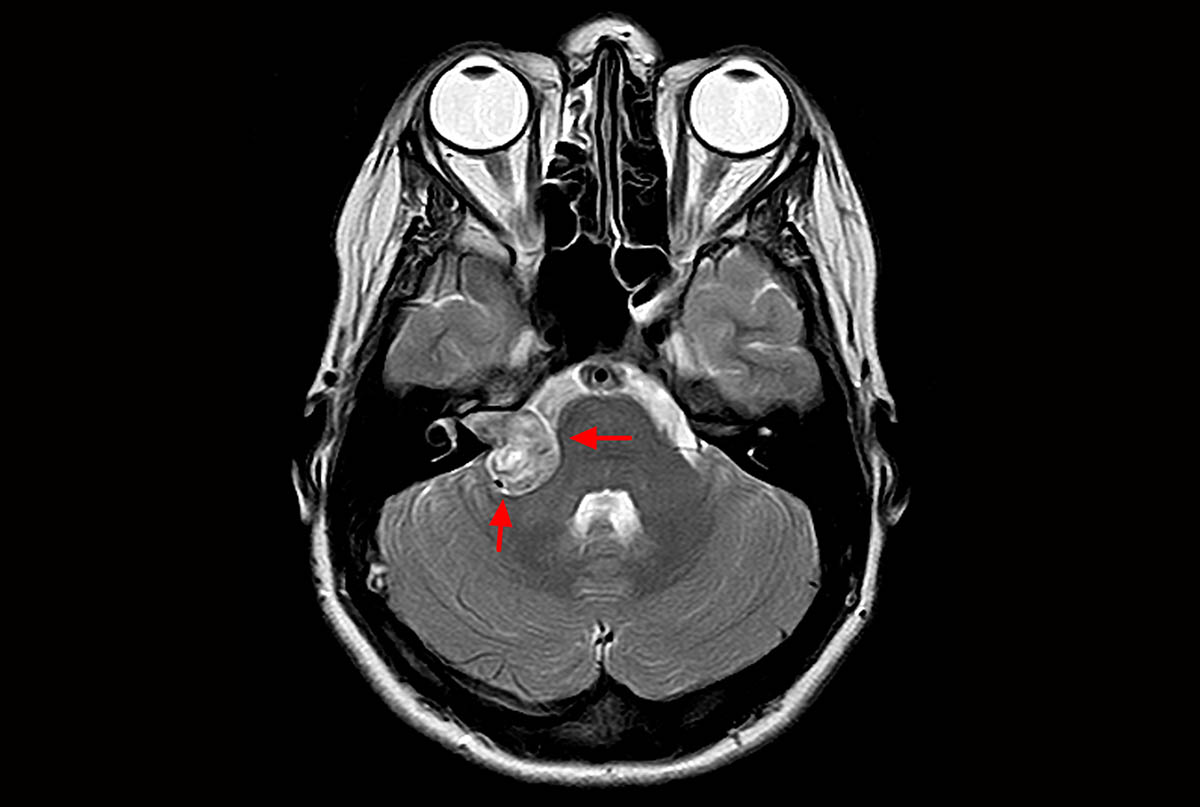

- методы визуализации (КТ височных костей, МРТ головного мозга) для исключения объемных образований или аномалий развития.

Невринома слухового нерва: полный гид по диагностике и методам лечения

Вы столкнулись с потерей слуха или шумом в ухе и подозреваете серьезное заболевание. Эта статья поможет разобраться в симптомах, современных методах диагностики и вариантах лечения невриномы слухового нерва, чтобы вернуть контроль над здоровьем.